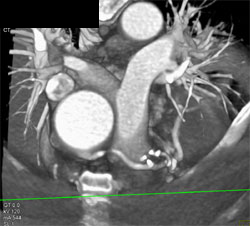

Dilated Pulmonary Outflow Tract